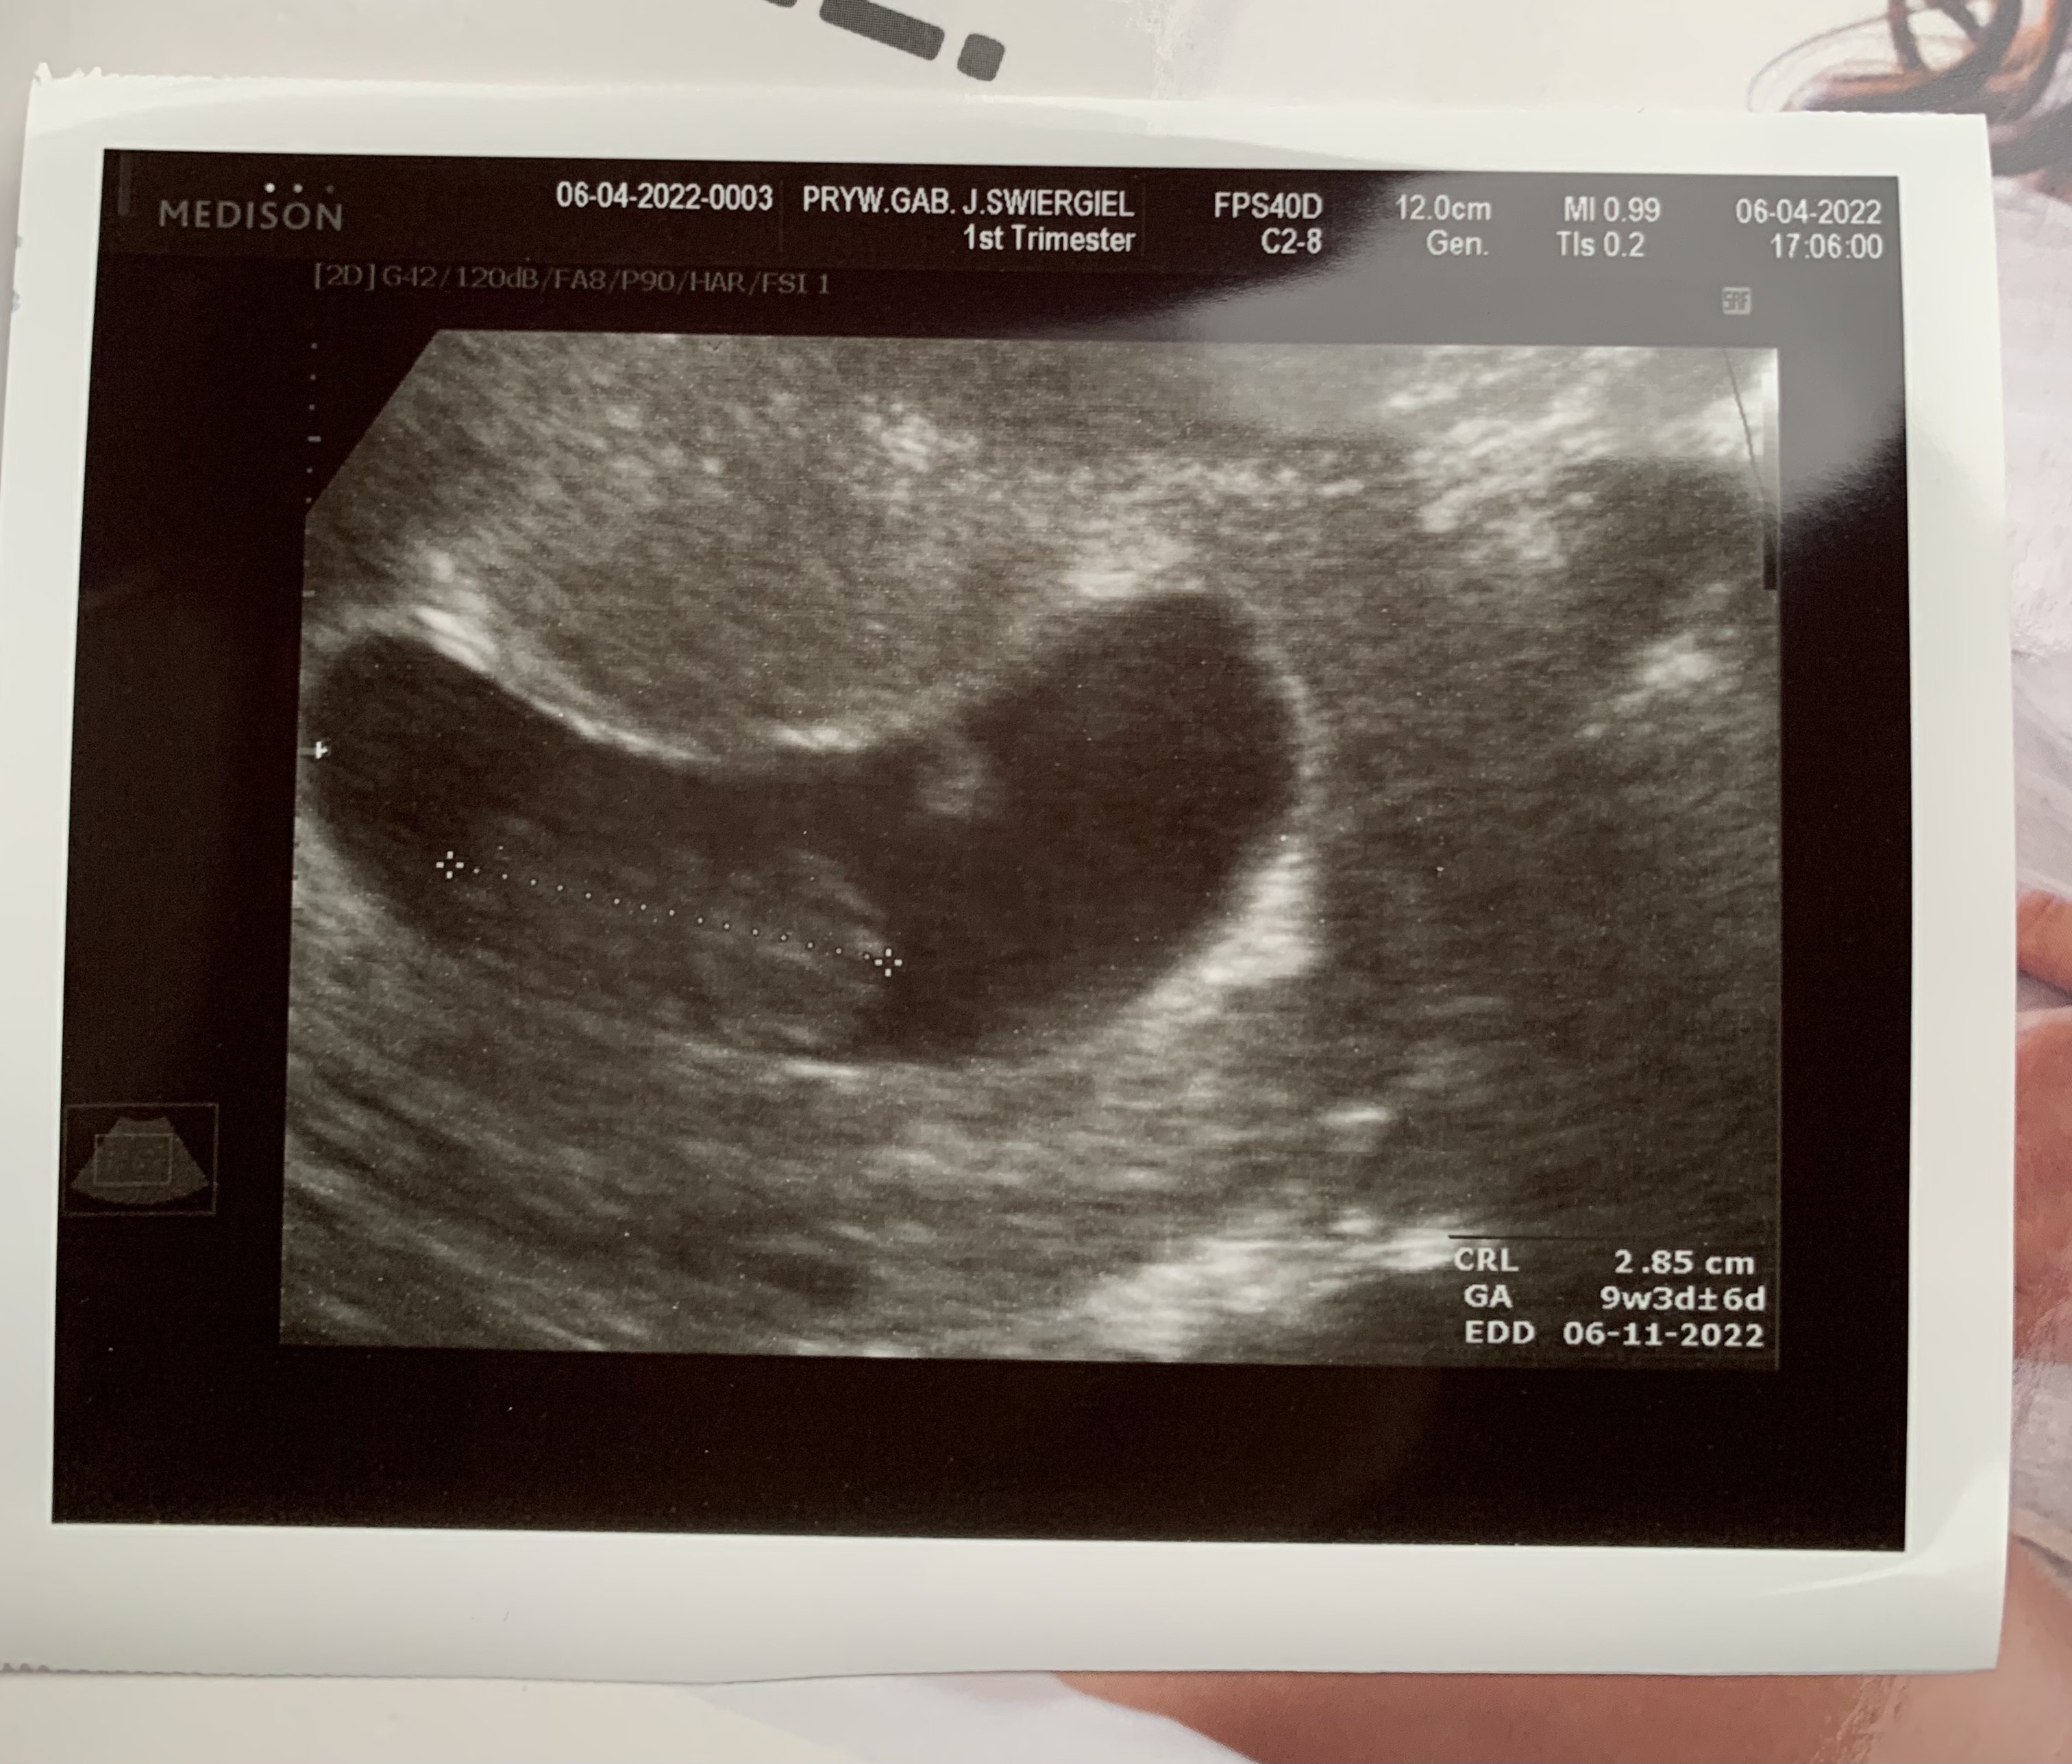

Troszkę niewyraźne, bo tym razem zrobił mi usg przez brzuch. Z bobo wszystko w porządku 🥰🥰 Są rączki, nóżki, tułów, główka, bije serduszko. Jestem szczęśliwa, bardzo się stresowałam tą wizytą 😌😌

Załączniki

• 272665FA-E57F-42FE-A053-079B6FE5B406.jpeg